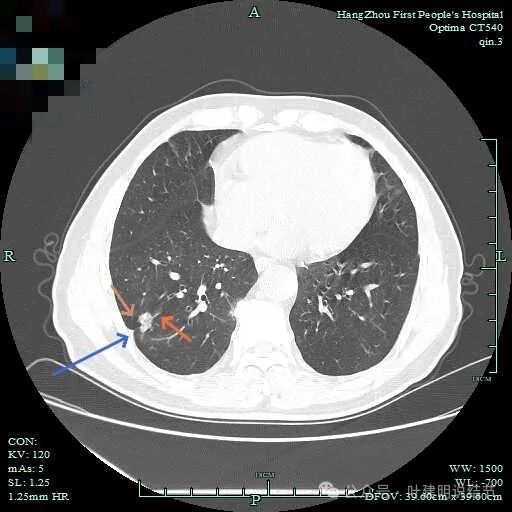

先看主病灶情况:

病灶出现,整体轮廓较清,胸膜略有牵拉。

密度不均匀,胸膜有轻微牵拉,边上有磨玻璃成分。

混合偏实性密度,瘤肺边界清,胸膜有牵拉。

表面不平,有小血管进入,整体轮廓与边界清。

明显胸膜牵拉以及血管进入,灶内密度不纯。